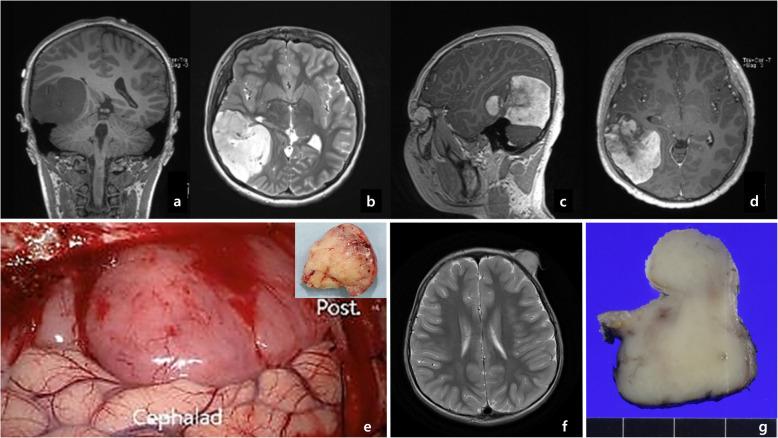

One case of TPR-NTRK1 fusion-positive intracranial, extra-axial, high-grade undifferentiated sarcoma (12-year-old boy), one case of LMNA-NTRK1 fusion-positive low-grade infantile fibrosarcoma of the forehead (3-year-old boy), one case of ETV6-NTRK3 fusion-positive inflammatory myofibroblastic tumor (IMT) (3-months-old girl), and six cases of ETV6-NTRK3 fusion-positive infantile fibrosarcoma (median age: 2.6 months, range: 1.6-5.6 months, M: F = 5:1) were reviewed. The Trk immunopositivity patterns were distinct, depending on what fusion genes were present. We observed nuclear positivity in TPR-NTRK1 fusion-positive sarcoma, nuclear membrane positivity in LMNA-NTRK1 fusion-positive sarcoma, and both cytoplasmic and nuclear positivity in ETV6-NTRK3 fusion-positive IMT and infantile fibrosarcomas. Also, the TPR-NTRK1 fusion-positive sarcoma showed robust positivity for CD34/nestin, and also showed high mitotic rate. The LMNA-NTRK1 fusion-positive sarcoma revealed CD34/S100 protein/nestin/CD10 coexpression, and a low mitotic rate. The IMT with ETV6-NTRK3 fusion expressed SMA. Six infantile fibrosarcomas with ETV6-NTRK3 fusion showed variable coexpression of nestin (6/6)/CD10 (4/5)/ S100 protein (3/6).

All cases of NTRK1 and NTRK3 fusion-positive pediatric tumors robustly expressed the Trk protein. A Trk immunopositive pattern and CD34/S100/nestin/CD10/SMA immunohistochemical expression may suggest the presence of NTRK fusion partner genes. LMNA-NTRK1 fusion sarcoma might be a low-grade subtype of infantile fibrosarcoma. Interestingly, more than half of the infantile fibrosarcoma cases were positive for S100 protein and CD10. The follow-up period of TPR-NTRK1 and LMNA-NTRK1 fusion-positive tumors are not enough to predict prognosis. However, ETV6-NTRK3 fusion-positive infantile fibrosarcomas showed an excellent prognosis with no evidence of disease for an average of 11.7 years, after gross total resection of the tumor.